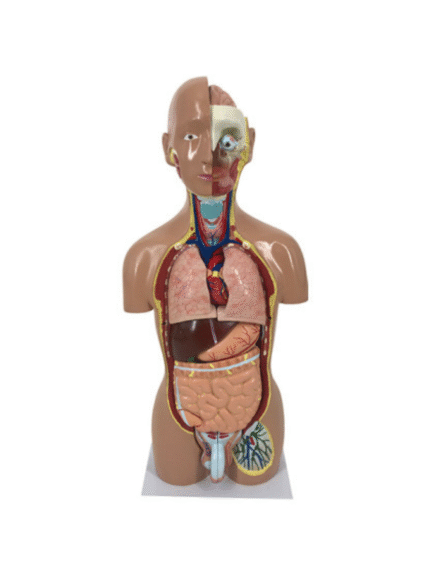

ATL-13 HUMAEN TORSO MALE 65CM WITH HARD ORGANS